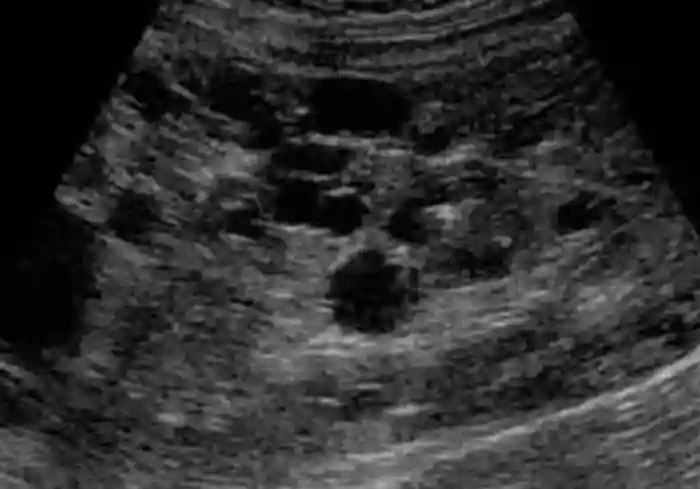

想诊断多囊肾病,用超声波是最快捷的。B超的局限在于没法探查过小的囊肿。在患病猫咪出生之时,肾脏中的囊肿可能只有1mm或者更小,在大小超过2mm之前,一般是难以被察觉的。

在经验丰富的医师手上,B超的准确度不输基因检测,早至两个月大就可以查出猫咪是否患有多囊肾病,但这对医生的水平要求太高,往往不实际。所以用b超检测多囊肾最好等猫咪9至10个月之后,这时候的准确度大致能达到91%到98%。